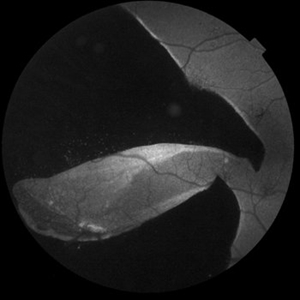

Combined Traction Rhegmatogenous Detachment

Oct 17 2024 by Hemanth Murthy, MBBS, MD, FASRS

A 68 year old male presented with a shadow in the left eye since 3 days. He was a known diabetic and hypertensive for 20 years. Vision was 20/40 in right eye and 20/60 in left eye. Fundus examination showed Proliferative diabetic retinopathy in right eye and Proliferative diabetic retinopathy with combined traction rhegmatogenous detachment in left eye.

Photographer: Mr Veda Vyas

Condition/keywords: combined retinal detachment, proliferative diabetic retinopathy (PDR)